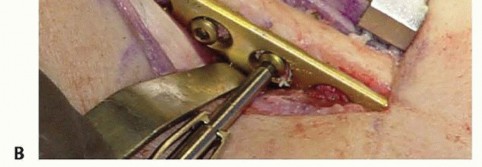

With the diaphysis exposed, we apply the dedicated cutting jig. The jig is temporarily fixed to the bone using bicortical screws. We utilize a sharp, cooled oscillating saw to execute the osteotomy. Copious cold saline irrigation is non-negotiable during the cutting phase to prevent thermal necrosis of the bone ends, which is a major contributor to nonunion. We make the proximal cut first, followed by the distal cut, removing the precisely templated wafer of bone. The oblique nature of the cut (usually 45 degrees) allows the bone ends to slide seamlessly together without rotational malalignment.

Following the resection, the compression device integrated into the jig is activated. We slowly and deliberately compress the osteotomy site until